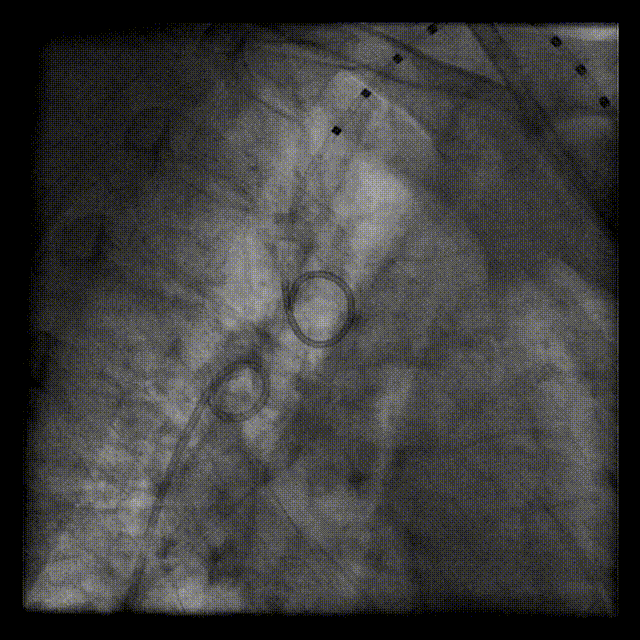

6Fr Cook鞘和14Fr Cook鞘沿通路轻柔操作,先后对离断部位进行扩张。

鞘管扩张通路

弓离断处送入39mm Cheatham-Platinum覆膜支架,选用20mmNuMED BiB球囊扩张

释放覆膜支架